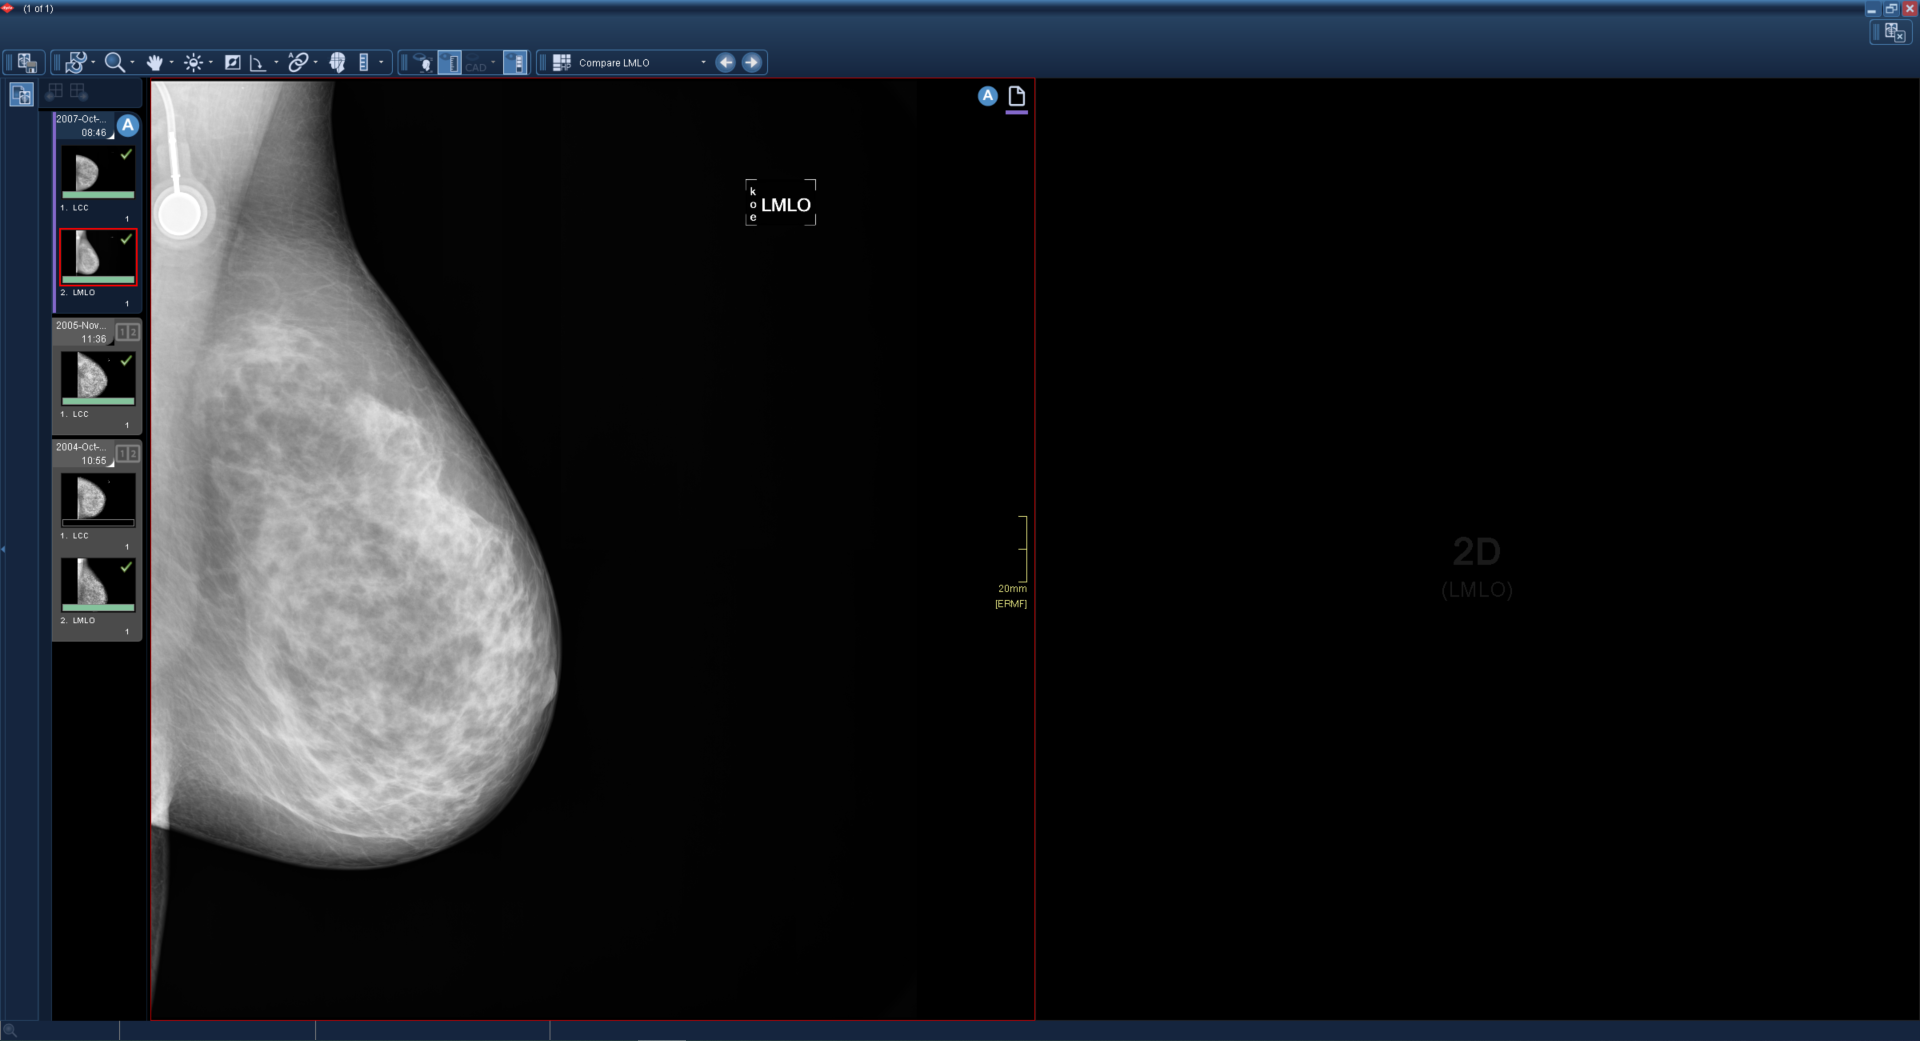

Αν η τρέχουσα μονάδα είναι διαθέσιμη σε μία από τις συγκριτικές εξετάσεις, αλλά κανένα από τα σύνολα δεδομένων εικόνας της δεν ταιριάζει με τον απαιτούμενο τύπο προβολής (για παράδειγμα, μαστογραφία CC) ενός παραθύρου, το εν λόγω παράθυρο είναι μαύρο. Χρησιμοποιήστε τις συντομεύσεις πλοήγησης για να δείτε τις άλλες συγκριτικές εξετάσεις. Επιπλέον, αν η τελευταία εξέταση είναι ήδη σε προβολή, χρησιμοποιώντας τις συντομεύσεις πλοήγησης εμφανίζονται επιπλέον μαύρα παράθυρα (βλ. παράδειγμα 2).

2

Αν η πρώτη προγενέστερη εξέταση δεν έχει προβολή σύγκρισης, το δεύτερο παράθυρο είναι μαύρο και δεν υπάρχουν διαθέσιμα βέλη. Χρησιμοποιήστε τις συντομεύσεις πλοήγησης για να μεταβείτε στην επόμενη προγενέστερη εξέταση.